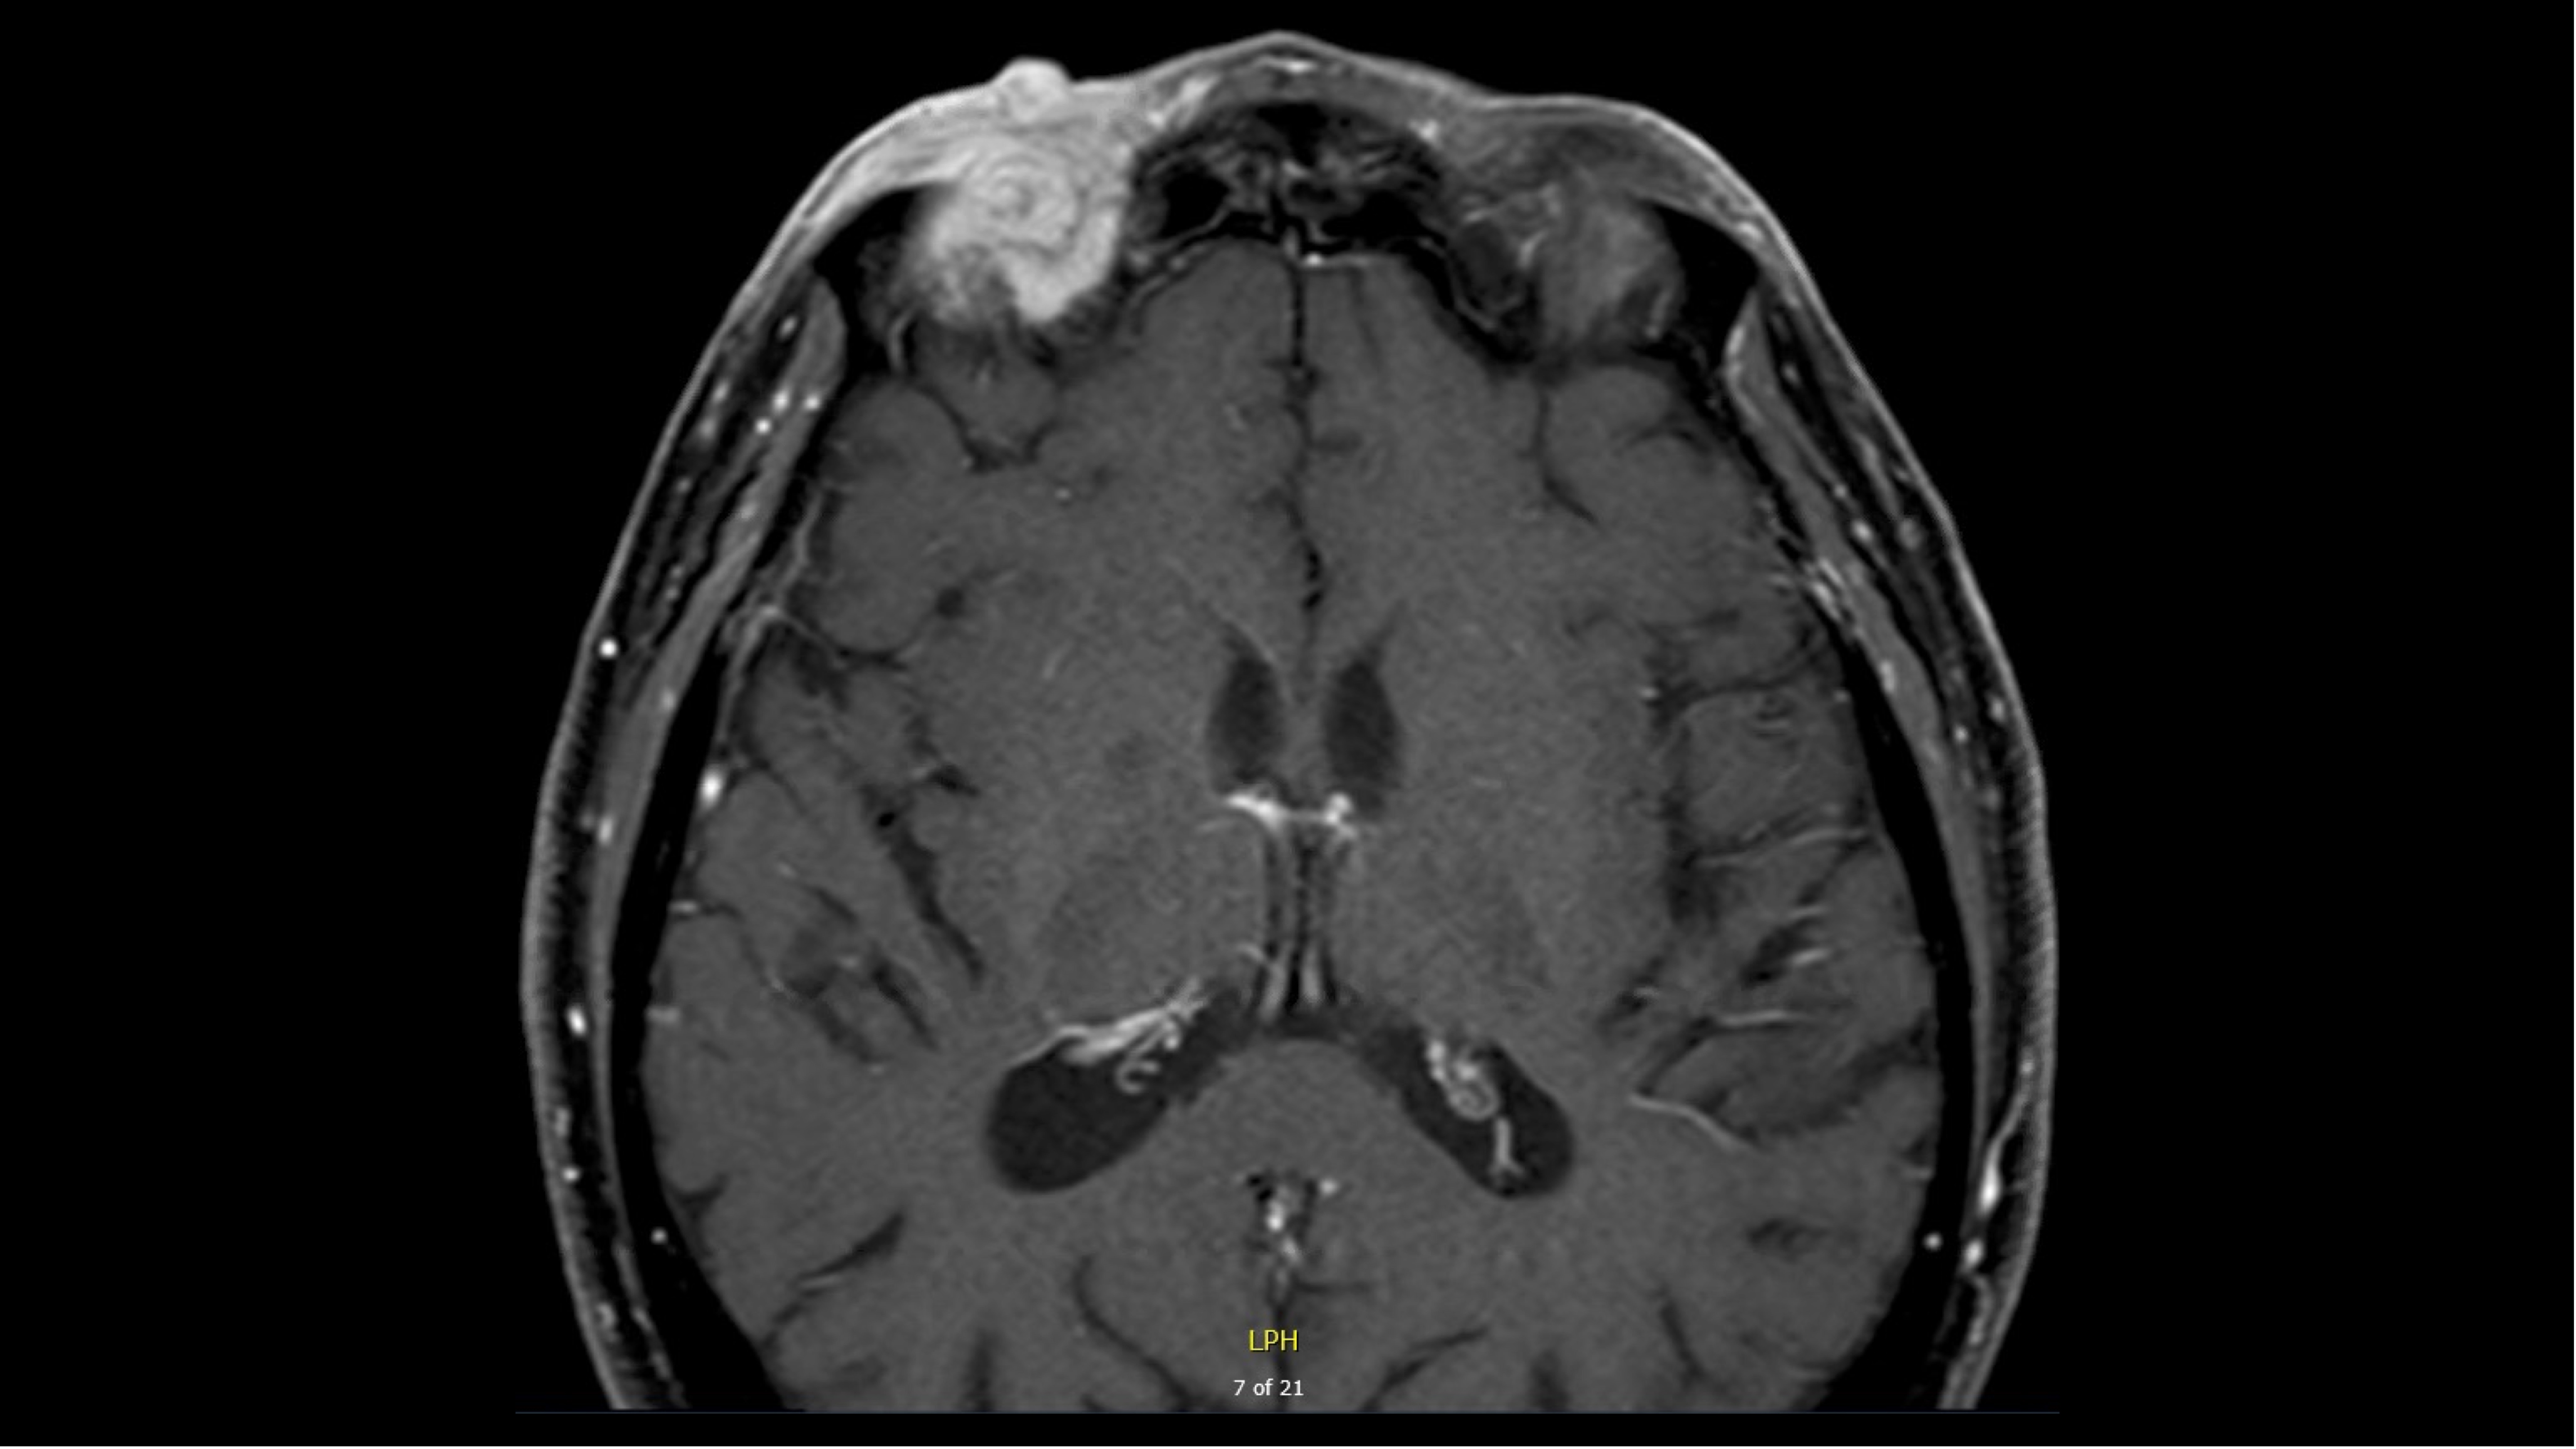

Case 1 - HPI

- Male in the 8th decade of life

- Presents with a 2.8 cm poorly differentiated peri-orbital CSCC

- Outside PET-CT showed no evidence of regional or metastatic disease

- MRI demonstrated:

T1, pre-contrast image (used with patient permission)